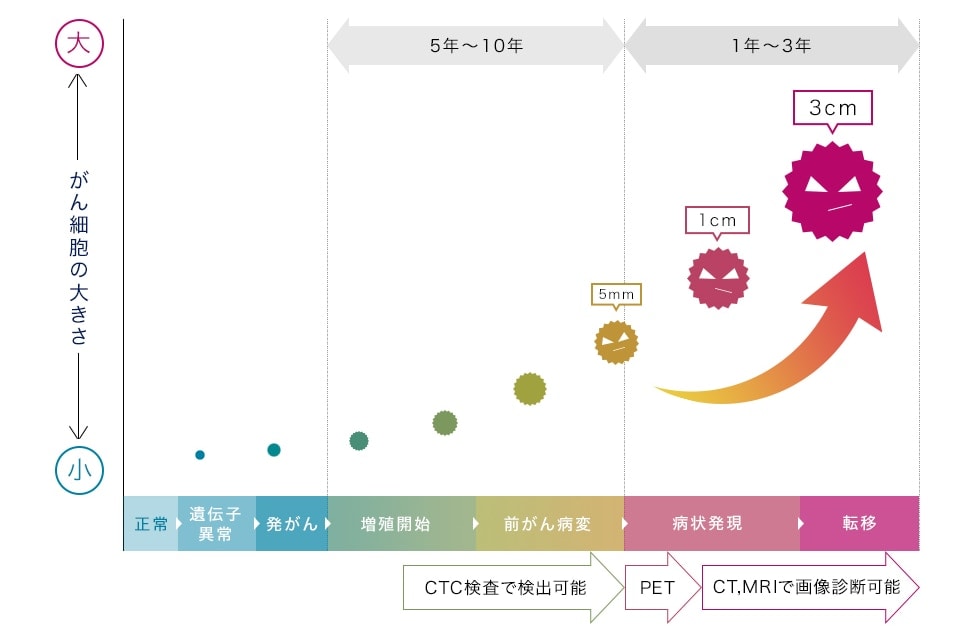

通常PETは5mm以上、CT、MRIでは10mm以上成長していないがん細胞は検知できません。そのため当病院では、CTC検査を行います。CTC検査とは血管の中を動き回っているがんの種やがん細胞の死骸を発見することができる検査になります。

これにより通常5mm以上でないと発見できないがん細胞を2mmの段階で発見が可能です。このCTC検査で早期発見しがんと戦うことが私たちが考える一番の選択だと思いますし、私たちはその力になれればと考えています。

がん細胞は、PETで5mm以上、CT、MRIで10mm以上の眼に見える大きさにならないと発見することができません。しかしながら、このCTC検査は、眼に見える「固形のがん」ではなく、「血液の中にあるがん細胞」をみるため、眼に見える大きさになる前にがん細胞の有無を確認することができます。

以下が、がん細胞が眼で確認できるまでの成長イメージです。

がん細胞は目に見えるサイズから急激に成長する

がん細胞は、画像に映る5mmから短期間で急激に成長します。ただしがん細胞そのものが突然できるわけではなく、5mmに至るまで長期間の時間をかけて細胞分裂を繰り返しながら成長します。(成長速度は人により異なります)

この成長段階で、血液中に流れているCTCを検査することが、

「早期発見」や「転移・再発の予防」につながります。